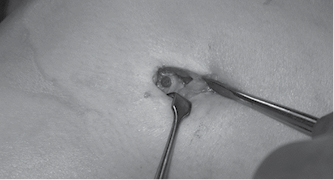

Un año posterior a la cirugía, acudió a consulta por presencia de dolor lateral a nivel de inserción distal de banda iliotibial en rodilla izquierda; se le indicó continuar con terapia física. Seis meses después acudió nuevamente con persistencia del dolor y de mayor intensidad, acompañado de contractura de banda iliotibial y dolor al flexionar con disminución en arcos de movimiento y presencia de protrusión de un pin en el Área Subcutánea del cóndilo femoral lateral de rodilla, con adecuada estabilidad ligamentaria. Se realizó resonancia magnética de rodilla, donde se observó fractura y migración del pin proximal hacia la región lateral de la rodilla sobre el trayecto de la banda iliotibial y presencia de inflamación (Figuras 1 y 2).

Se decidió realizar procedimiento quirúrgico para retiro de pin bioabsorbible; en el procedimiento se observó extrusión de 1 cm del pin con borde cortante reductible (Figura 3) y al retirarlo se observó presencia de ruptura del pin (Figura 4). Posterior a la cirugía se corroboraron arcos de movimiento completos (0o-120o) con adecuada estabilidad ligamentaria. Se continuó vigilancia del paciente, con rodilla izquierda sin presencia de dolor o derrame articular, con arcos de movimiento completos, sin datos de inestabilidad, tolerando actividad física y con escalas de funcionalidad adecuadas.

Figura 3: Imagen quirúrgica de la porción del pin bioabsorbible protruida hacia la región lateral extraarticular. En la esquina inferior derecha se observa la porción fracturada del pin retirada en cirugía.